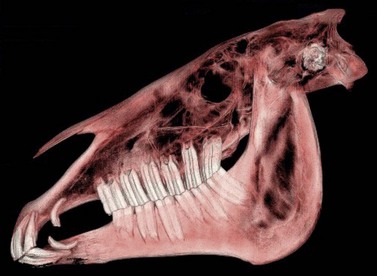

When exposing bone overlying the apex of the mandibular 1st molar (i.e., Triadan 309 or 409), care should be taken to avoid damaging the facial artery and vein and the parotid salivary duct, which cross the lateral surface of the mandible along the rostral border of the masseter muscle close to the site of osteotomy (Fig. 20.40). Reflecting these structures away from the site of trephination may be necessary. When exposing bone overlying the apex of a maxillary premolar (i.e., Triadan 106–108 or 206–208), care should be taken to avoid damaging the infraorbital nerve and facial artery and vein, which lie in close proximity to the site of osteotomy. The apex of any one of the three maxillary premolars is exposed by removing the external lamina of the maxilla overlying it, usually with a trephine. The apices of the maxillary molars (i.e., Triadan 109–111 or 209–211) reside within the paranasal sinuses (Fig. 20.41) and can be exposed through a trephine hole or through an osteoplastic flap into the paranasal sinuses.

image

Fig. 20.41 Computed tomographic image of a head showing the relationship between the paranasal sinuses and the maxillary molars (Triadan 109–111 and 209–211).

(Image is courtesy of Luis Velazquez, University of Mexico.)